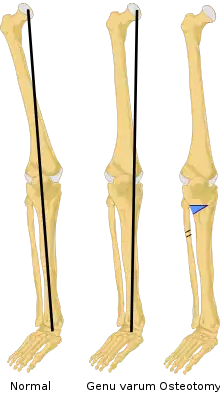

An osteotomy is a surgical operation whereby a bone is cut to shorten or lengthen it or to change its alignment. It is sometimes performed to correct a hallux valgus, or to straighten a bone that has healed crookedly following a fracture. It is also used to correct a coxa vara, genu valgum, and genu varum. The operation is done under a general anaesthetic.[1]

Knee osteotomy is commonly used to realign arthritic damage on one side of the knee. The goal is to shift the patient's body weight off the damaged area to the other side of the knee, where the cartilage is still healthy. Surgeons remove a wedge of the tibia from underneath the healthy side of the knee, which allows the tibia and femur to bend away from the damaged cartilage.[7]

The location of the removed wedge of bone depends on where osteoarthritis has damaged the knee cartilage. The most common type of osteotomy performed on arthritic knees is a high tibial osteotomy, which addresses cartilage damage on the inside (medial) portion of the knee. The procedure usually takes 60 to 90 minutes to perform.[9]

During a high tibial osteotomy, surgeons remove a wedge of bone from the outside of the knee, which causes the leg to bend slightly inward. This resembles the realigning of a bowlegged knee to a knock-kneed position. The patient's weight is transferred to the outside (lateral) portion of the knee, where the cartilage is still healthy.[10]